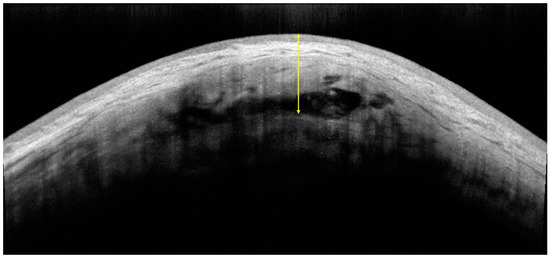

2.3.1. Bleb Evaluation Using OCTA

- AS-OCTA Image Acquisition and Processing